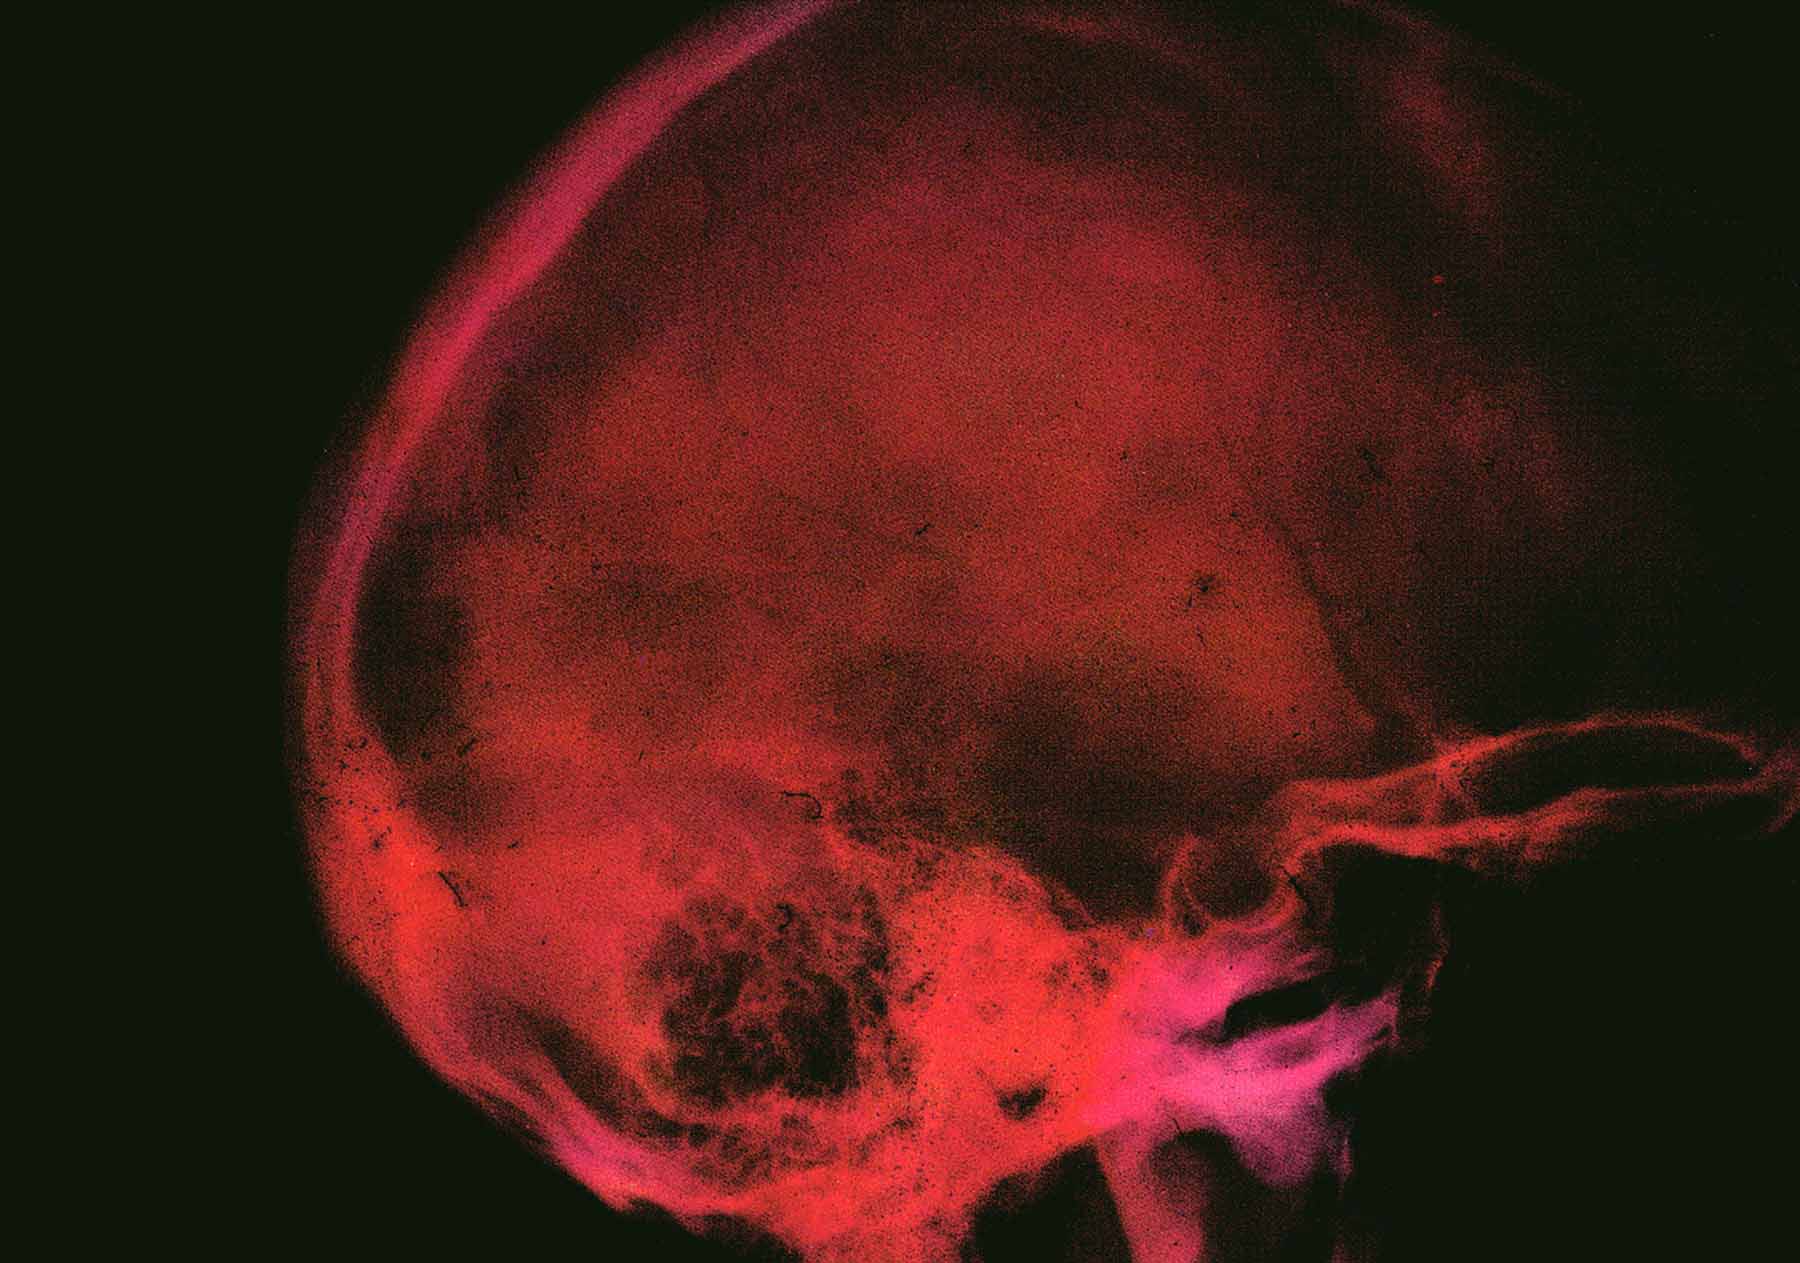

Cada una de les peces porten el nom d’una de les frases-grafitis que varen realitzar-se en aquella època, de manera que, a través dels motius literaris espontanis del passat, aquesta artista ens connecta amb les nostres circumstàncies actuals.La peça central d’aquesta esposició està construïda amb transparéncies mèdiques que es superposen creant un ampli espectre de la nostra interioritat.

I amb la vibració del terra, els cruixits i rumors de les potències en acció, Hans Castorp va sotjar en aquella finestra esblanqueïda, va sotjar l’ossada nua de Joachim Ziemssen. L’estern coincidia amb l’espina dorsal formant una columna fosca, cartilaginosa. Les costelles de davant es creuaven amb les de l’esquena, que semblaven més pàl.lides. A dalt, les clavícules es bifurcaven, arquejades cap ambdós costats, i en el suau embolcall de la carn es veia, eixut i agusat, l’esquelet dels muscles i dels dalts dels braços de Joachim.

L’espai pectoral era clar, però si distingien unes vetes, taques fosques, un embullat negrós.

-Una estampa clara- a dir el metge- …”